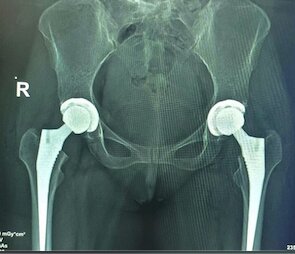

Total Hip Replacement (THR)

Minimally Invasive Muscle-Sparing Hip Replacement

Direct Anterior Hip Replacement